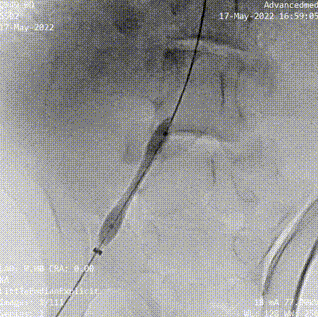

參與此次動(dòng)物實(shí)驗(yàn)的臨床主任醫(yī)師——中山大學(xué)附屬第七醫(yī)院特聘教授、復(fù)星醫(yī)療集團(tuán)心血管技術(shù)總監(jiān)彭宇程向億歐大健康介紹道,“本次動(dòng)物實(shí)驗(yàn)中,我們用機(jī)器人輔助完成了PCI、腎動(dòng)脈支架植入以及下肢血管覆膜支架(由深圳創(chuàng)心醫(yī)療提供)植入等3種常見血管介入手術(shù)類型,說明了這個(gè)平臺(tái)的兼容性還是挺好的,同時(shí)在手術(shù)中,導(dǎo)絲導(dǎo)管操作、球囊支架輸送都能夠順利實(shí)施?!?/p>

臨床上病人可能兼有多種疾病,醫(yī)生也有開展多種手術(shù)的要求,從意義來看,本次動(dòng)物實(shí)驗(yàn)既驗(yàn)證了睿心醫(yī)療血管介入手術(shù)機(jī)器人平臺(tái)的可兼容性,是全球首次在一臺(tái)設(shè)備、不更換傳送裝置的情況下同時(shí)完成了冠脈、腎主動(dòng)脈和外周三個(gè)部位的支架手術(shù),同時(shí)實(shí)驗(yàn)的成功也為其下一步進(jìn)入人體臨床試驗(yàn)提供安全、有效證據(jù)和參考依據(jù)。

(腎動(dòng)脈導(dǎo)絲遞進(jìn))